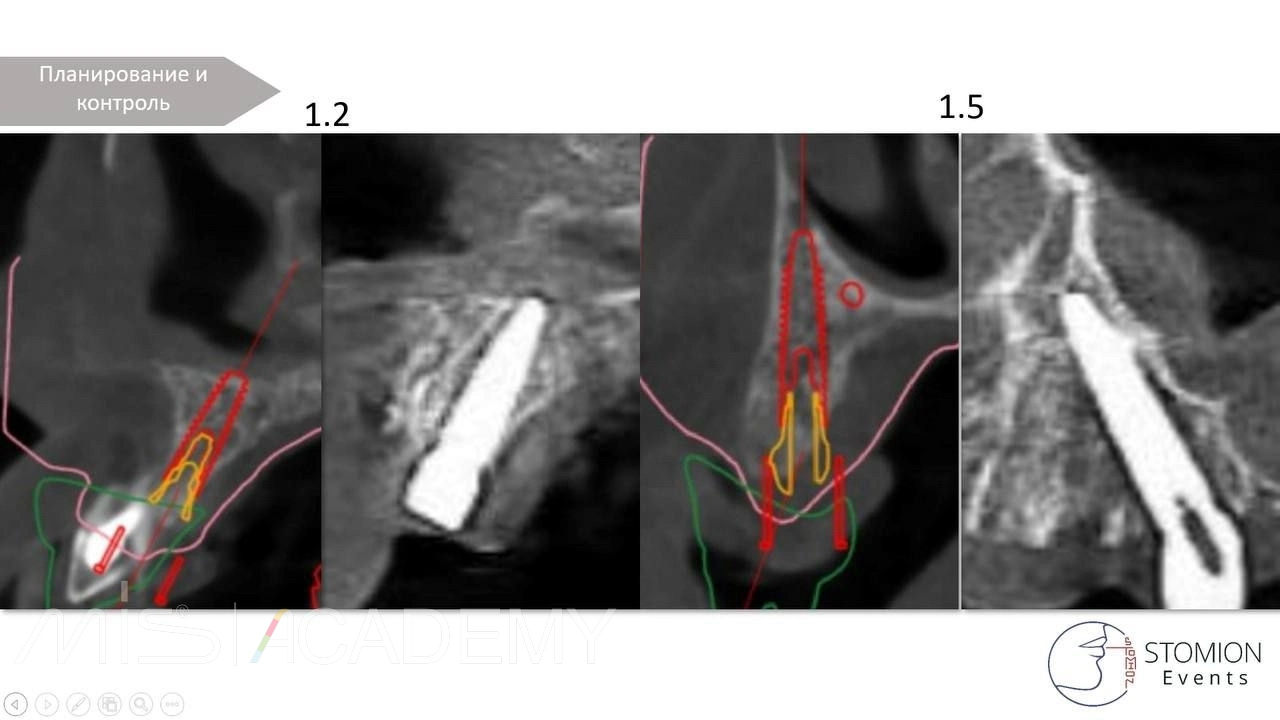

— MIS C1, коннекты во фронте, 30 градусов МЮ дистально.

— Навигация полнопротокольная, разборная, накостная.